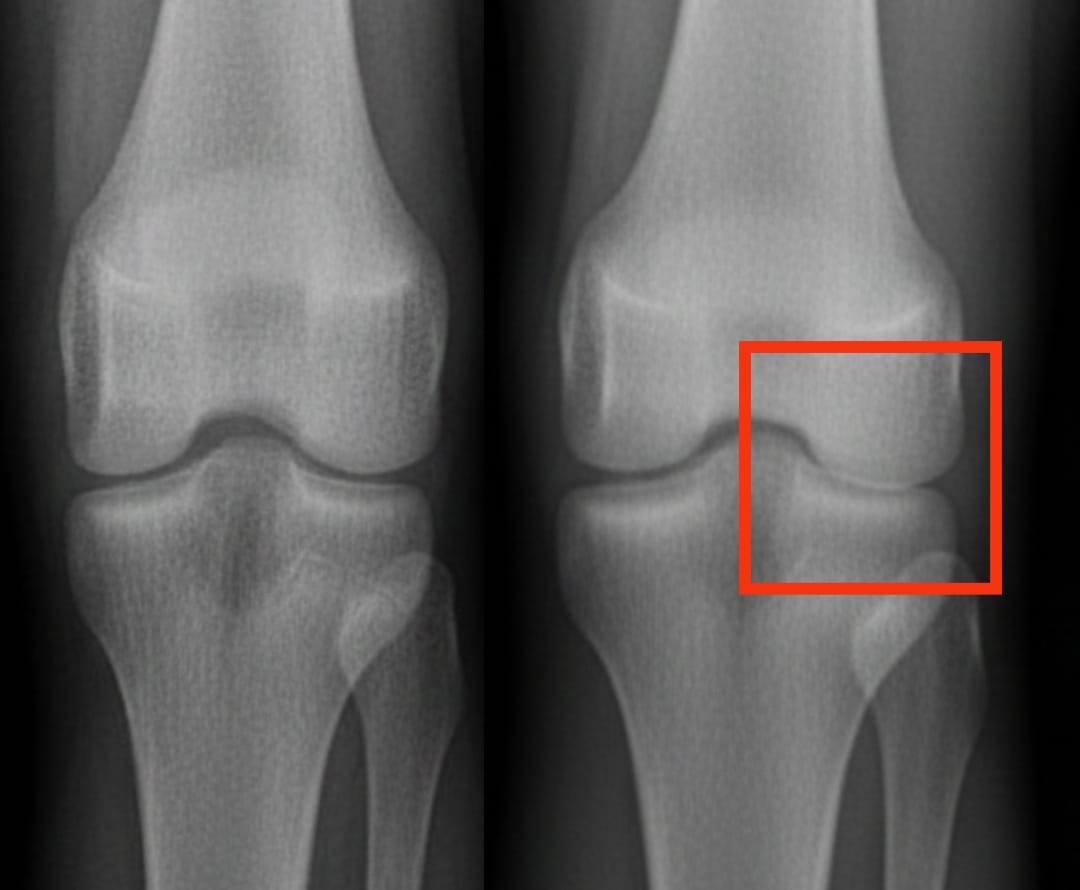

Kniearthrose betrifft weltweit Hundertmillionen Menschen. Sie ist durch den fortschreitenden Verschleiß des Knorpels gekennzeichnet, was zu Schmerzen und Bewegungseinschränkungen führt. Unter den angebotenen Lösungen weckt die Injektion von plättchenreichem Plasma zunehmend Interesse. Diese Behandlung nutzt das eigene Blut des Patienten, das mit Blutplättchen angereichert wird, um die Gewebereparatur zu stimulieren und Entzündungen zu reduzieren.

Eine aktuelle Analyse verglich die Wirksamkeit von plättchenreichem Plasma mit anderen gängigen Injektionen: Hyaluronsäure, Kortikosteroide und eine Kochsalzlösung als Placebo. Die Ergebnisse zeigen, dass plättchenreiches Plasma Schmerzen und Beweglichkeit nach sechs Monaten signifikant verbessert, wobei die Vorteile bis zu einem Jahr anhalten. Diese Verbesserungen sind ausgeprägter als die mit Hyaluronsäure oder Kortikosteroiden erzielten und deutlich besser als die des Placebos.